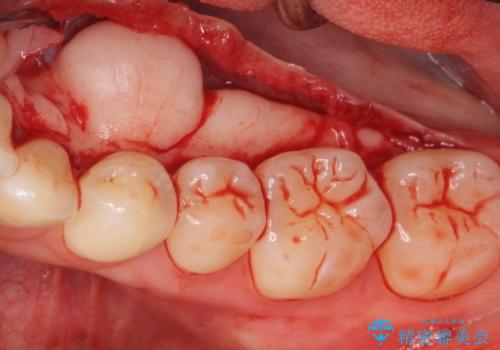

- 舌が下顎の骨隆起にあたって不快との事で来院。

静脈内鎮静麻酔を行い下顎骨隆起切除術を行いました。